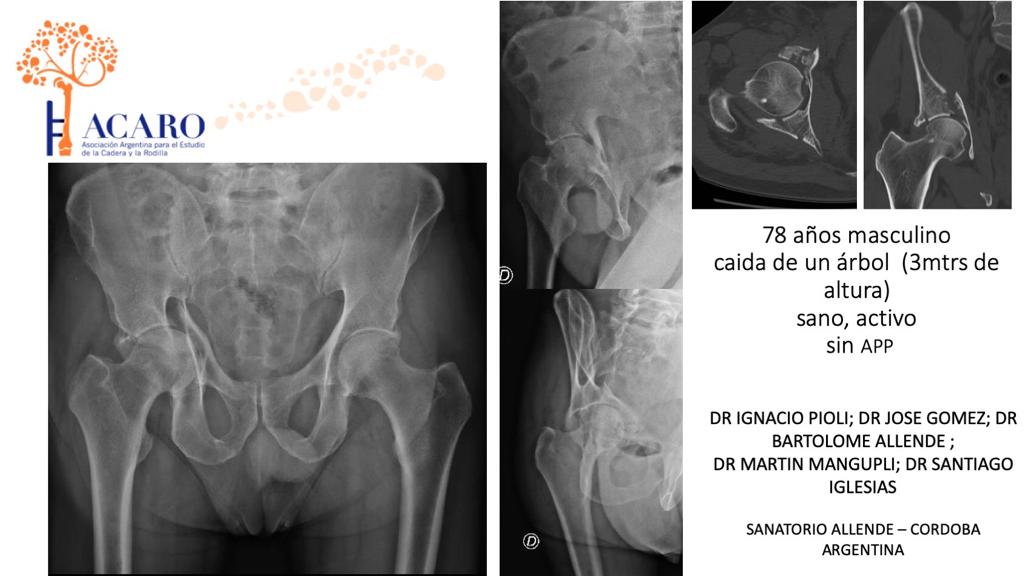

Nuevo caso problema! Tomate 5 minutos para ver algo interesante y continuar con tu práctica...vale la pena! 🤩💪🏻 #casoproblema #acaro #caderas